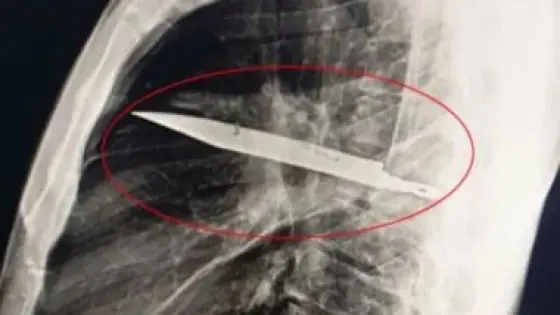

لقي عامل مصرعه في 15 مايو بالقاهرة، وذلك بعدما خرجت طلقة طائشة من سلاح أودت بحياته.

جاء ذلك فى إطار جهود أجهزة وزارة الداخلية لكشف ملابسات ما تبلغ لقسم شرطة 15 مايو، بإطلاق عيار نارى ووجود متوفى بأحد العقارات تحت الإنشاء بدائرة القسم، بالانتقال والفحص تم العثور على جثة (عامل بناء ، مقيم بدائرة مركز شرطة منفلوط بمحافظة أسيوط) بإحدى الغرف بشقة سكنية تحت الإنشاء وبها إصابات عبارة عن طلق نارى خرطوش بالرأس.

بالفحص وسؤال ( 6 عاملين بناء مقيمين صحبة المتوفى) قرروا بأنه حال تواجدهم بإحدى الغرف بالشقة محل الواقعة، وتواجد المتوفى داخل غرفة أخرى بذات الشقة نمى إلى سمعهم صوت طلق نارى ، وبإستبيان الأمر عثروا على جثة المتوفى على النحو المشار إليه وبجواره سلاح نارى “فرد خرطوش” يملكه (مقاول عمال ، مقيم بذات العنوان).

بالفحص تبين أنه حال تواجد المتوفى داخل الغرفة محل الواقعة قام بالعبث بالسلاح النارى المشار إليه مما أدى إلى خروج طلقة عن طريق الخطأ محدثةً إصابته التى أودت بحياته ، وعقب علم المقاول بالواقعة قام بإخفاء السلاح النارى .